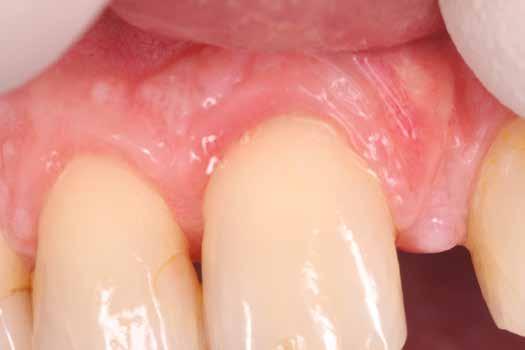

A megfelelő vizuális kontroll és az izolálhatóság kedvéért lebenyt alakítottunk [4. kép]. Így az abszolút izolálás már kivitelezhető volt és kofferdám izolálásban kezeltük a léziót [5. kép]. Mivel az elváltozás nem látható területen helyezkedett el, illetve a kavitás kis kiterjedését figyelembe véve kalcium-szilikát bázisú anyagot választottunk a restauráláshoz (Biodentine, Septodont) [6. kép]. Miután letelt a választott anyagunk kötési ideje (12 perc), zártuk a lebenyt [6. kép]. Páciensünk azóta is panaszmentes, kétéves kontrollon állapota rendben volt [7. és 8. kép].

Ötvenes éveiben járó hölgyet fogorvosa irányította hozzánk a bal alsó 4-es fogának nagy méretű reszorpciójával [9. kép]. A hölgy ragaszkodott foga megmentéséhez, így a kezelés megtervezéséhez CBCT felvételt készítettünk a fogról [10. kép]. A felvételen a Patel-féle klasszifikáció szerinti Patel 3Ap reszorpciós elváltozás látható. A szájüregi vizsgálat során a fog bukkális felszínén gyulladt ínyt, mély parodontális tasakot és a fog nyaki részén, a foganyagon átsejlő reszorpciós lacunát találtunk [11. kép]. A fog szenzibilitás vizsgálat során nem reagált hideg ingerlésre. A pulpális érintettség miatt elvégeztük a fog trepanálását, majd lebenyt alakítottunk a kavitás láthatóvá tételéhez [12. kép]

volt. Két hónapos kontrollon a fog teljesen ép, az íny tökéletes kitapadását tapasztaltuk [18. és 19. kép]. Szondázási mélység a bukkális oldalon mindenhol 2 mm alatt volt.